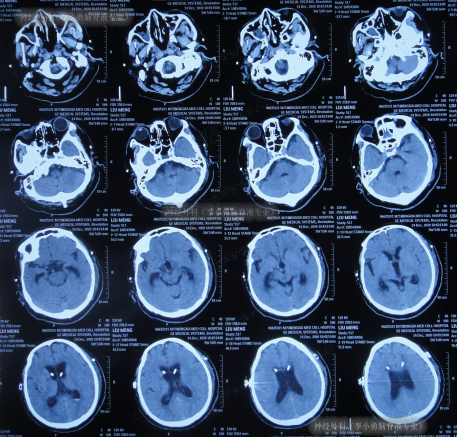

住院1周左右时间,期间曾3次查头颅CT(图-2)示脑室稍有扩张,但头晕症状慢慢消失,行走不稳缓解,认为“病情变好”出院。

图-2:3次查头颅CT